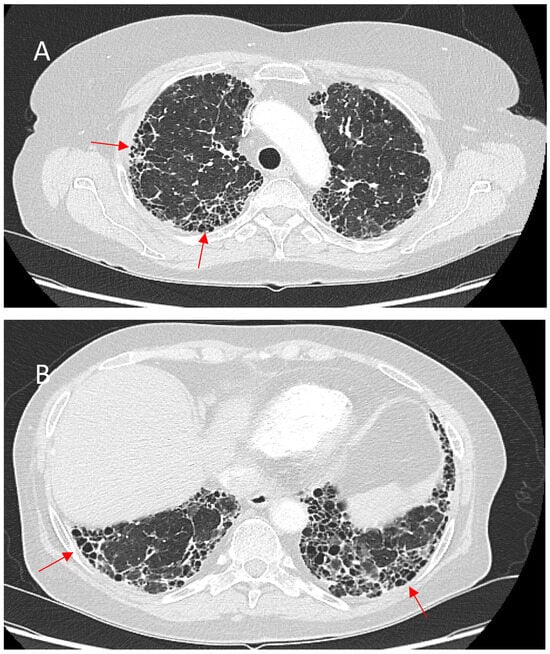

5. Radiological Aspects of Fibrotic Pulmonary Sarcoidosis

5.1. Key HRCT Findings in fPS

5.1.1. Micronodules and Ground-Glass Opacities (GGOs)

5.1.3. Honeycombing

5.1.4. Linear Fibrosis